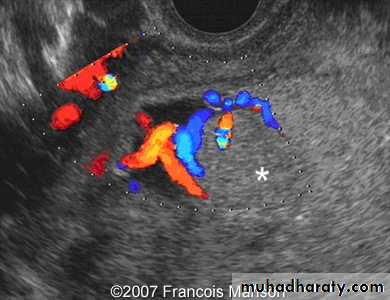

Doppler

Duplex in varicose veins